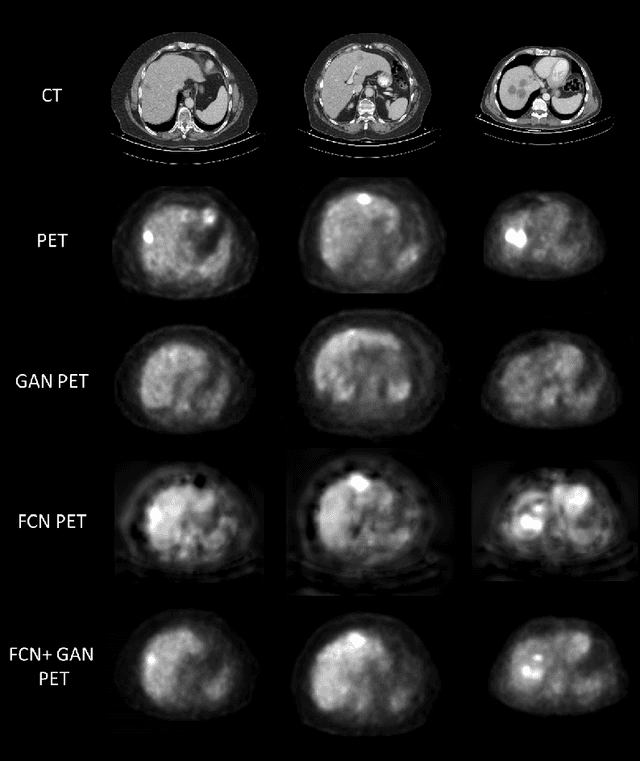

Abstract:In this work we present a novel system for generation of virtual PET images using CT scans. We combine a fully convolutional network (FCN) with a conditional generative adversarial network (GAN) to generate simulated PET data from given input CT data. The synthesized PET can be used for false-positive reduction in lesion detection solutions. Clinically, such solutions may enable lesion detection and drug treatment evaluation in a CT-only environment, thus reducing the need for the more expensive and radioactive PET/CT scan. Our dataset includes 60 PET/CT scans from Sheba Medical center. We used 23 scans for training and 37 for testing. Different schemes to achieve the synthesized output were qualitatively compared. Quantitative evaluation was conducted using an existing lesion detection software, combining the synthesized PET as a false positive reduction layer for the detection of malignant lesions in the liver. Current results look promising showing a 28% reduction in the average false positive per case from 2.9 to 2.1. The suggested solution is comprehensive and can be expanded to additional body organs, and different modalities.

Abstract:In this work we present a novel system for PET estimation using CT scans. We explore the use of fully convolutional networks (FCN) and conditional generative adversarial networks (GAN) to export PET data from CT data. Our dataset includes 25 pairs of PET and CT scans where 17 were used for training and 8 for testing. The system was tested for detection of malignant tumors in the liver region. Initial results look promising showing high detection performance with a TPR of 92.3% and FPR of 0.25 per case. Future work entails expansion of the current system to the entire body using a much larger dataset. Such a system can be used for tumor detection and drug treatment evaluation in a CT-only environment instead of the expansive and radioactive PET-CT scan.